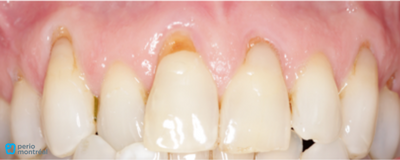

Before picture of gingival recession

- Multiple Class V composite lesions, some being defective

- Gingival recession ranging from 2 to 6 mm

- Adequate keratinized gingiva

This patient exhibited multiple lesions associated with gingival recession. Initial recession values varied from 2 mm to 6 mm and keratinized gingiva was adequate. Teeth #15 to 25 were treated.